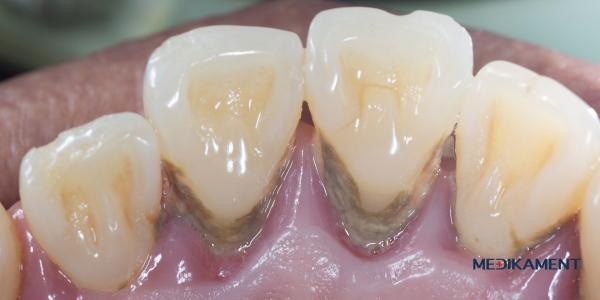

Paradentóza má charakteristický vzhľad a prejavy, ktoré sú často zreteľné najmä v ústnej dutine. Na prvý pohľad môže byť viditeľné začervenanie a opuch ďasien, ktoré sú pri tomto ochorení typicky citlivé a môžu krvácať, najmä pri čistení zubov alebo zjedení tvrdšej potravy. Povrch ďasien môže pôsobiť lesklým alebo napnutým dojmom, čo je spôsobené zápalom a opuchom.

S postupujúcim ochorením sa medzi zubami a ďasnami vytvárajú tzv. parodontálne vačky – hlbšie priestory, ktoré vznikajú oddelením ďasien od zubov. Tieto vačky sú často naplnené zápalovým exudátom a baktériami, ktoré ďalej poškodzujú tkanivá. Pri pohľade do ústnej dutiny môže zubný lekár alebo skúsený pozorovateľ spozorovať, že ďasná ustupujú a zuby začínajú vyzerať dlhšie, pretože ich spodná časť, ktorá je normálne zakrytá ďasnami, sa stáva viditeľnou.

V pokročilých štádiách paradentózy sa zuby môžu začať uvoľňovať, pretože dochádza k poškodeniu väzív a úbytku kostnej hmoty, ktorá ich drží na mieste. Môže sa objaviť tiež zápach z úst (halitóza), ktorý vzniká v dôsledku hromadenia baktérií a zápalových procesov. Pacienti môžu pociťovať aj bolesti alebo nepríjemný pocit v ďasnách, zvlášť pri žuvaní.

Celkovo paradentóza vyzerá ako zápalové a degeneratívne poškodenie ďasien a okolitých štruktúr zuba, ktoré vedie k ich postupnému ústupu, tvorbe hlbokých vačkov a narušeniu stability zubov. Preto je dôležité takéto príznaky neignorovať a vyhľadať odbornú pomoc čo najskôr.